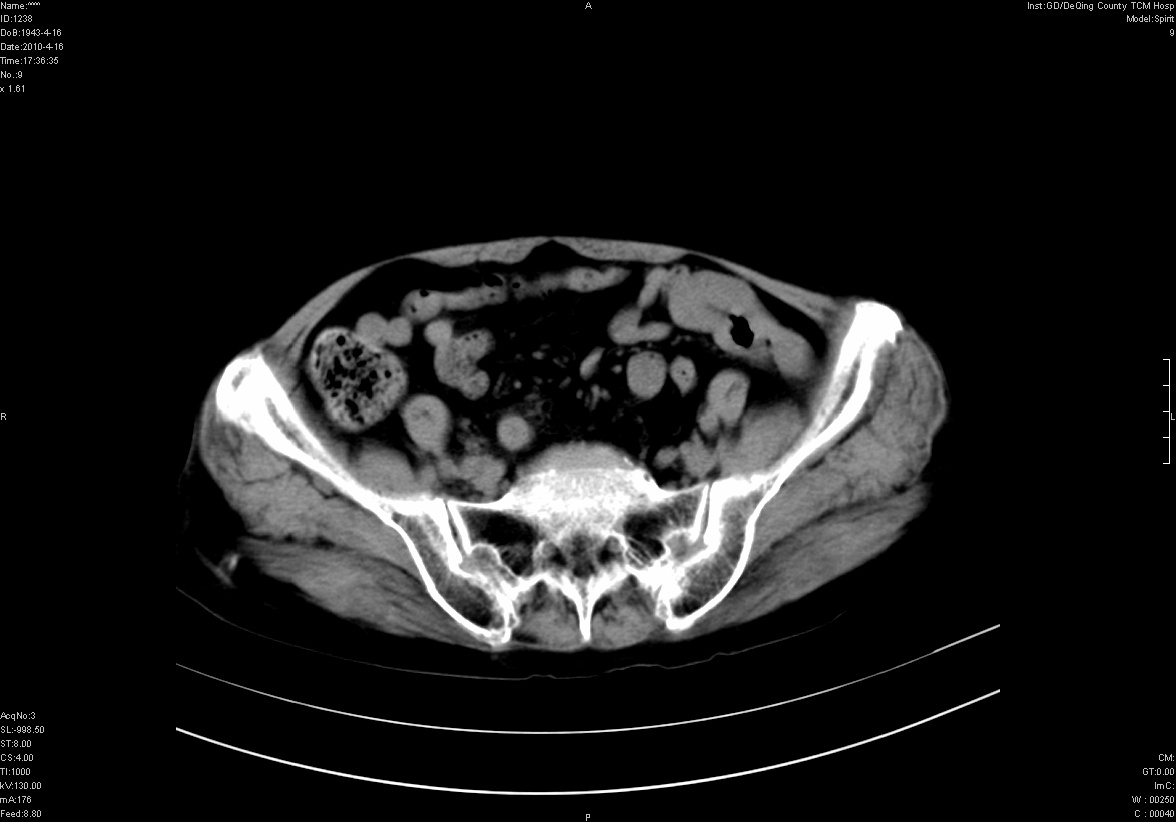

标题: CT25796:女,60岁,腹痛5天,请会诊??? [打印本页]

标题: CT25796:女,60岁,腹痛5天,请会诊???

是要我考虑粪石吗?引起阑尾炎

考虑卵巢畸胎瘤。

支持右侧盆腔畸胎瘤。

畸胎瘤

右侧附件畸胎瘤

不太像畸胎瘤,粪石。

考虑右侧卵巢畸胎瘤。

考虑右侧卵巢畸胎瘤

右侧卵巢畸胎瘤可能。